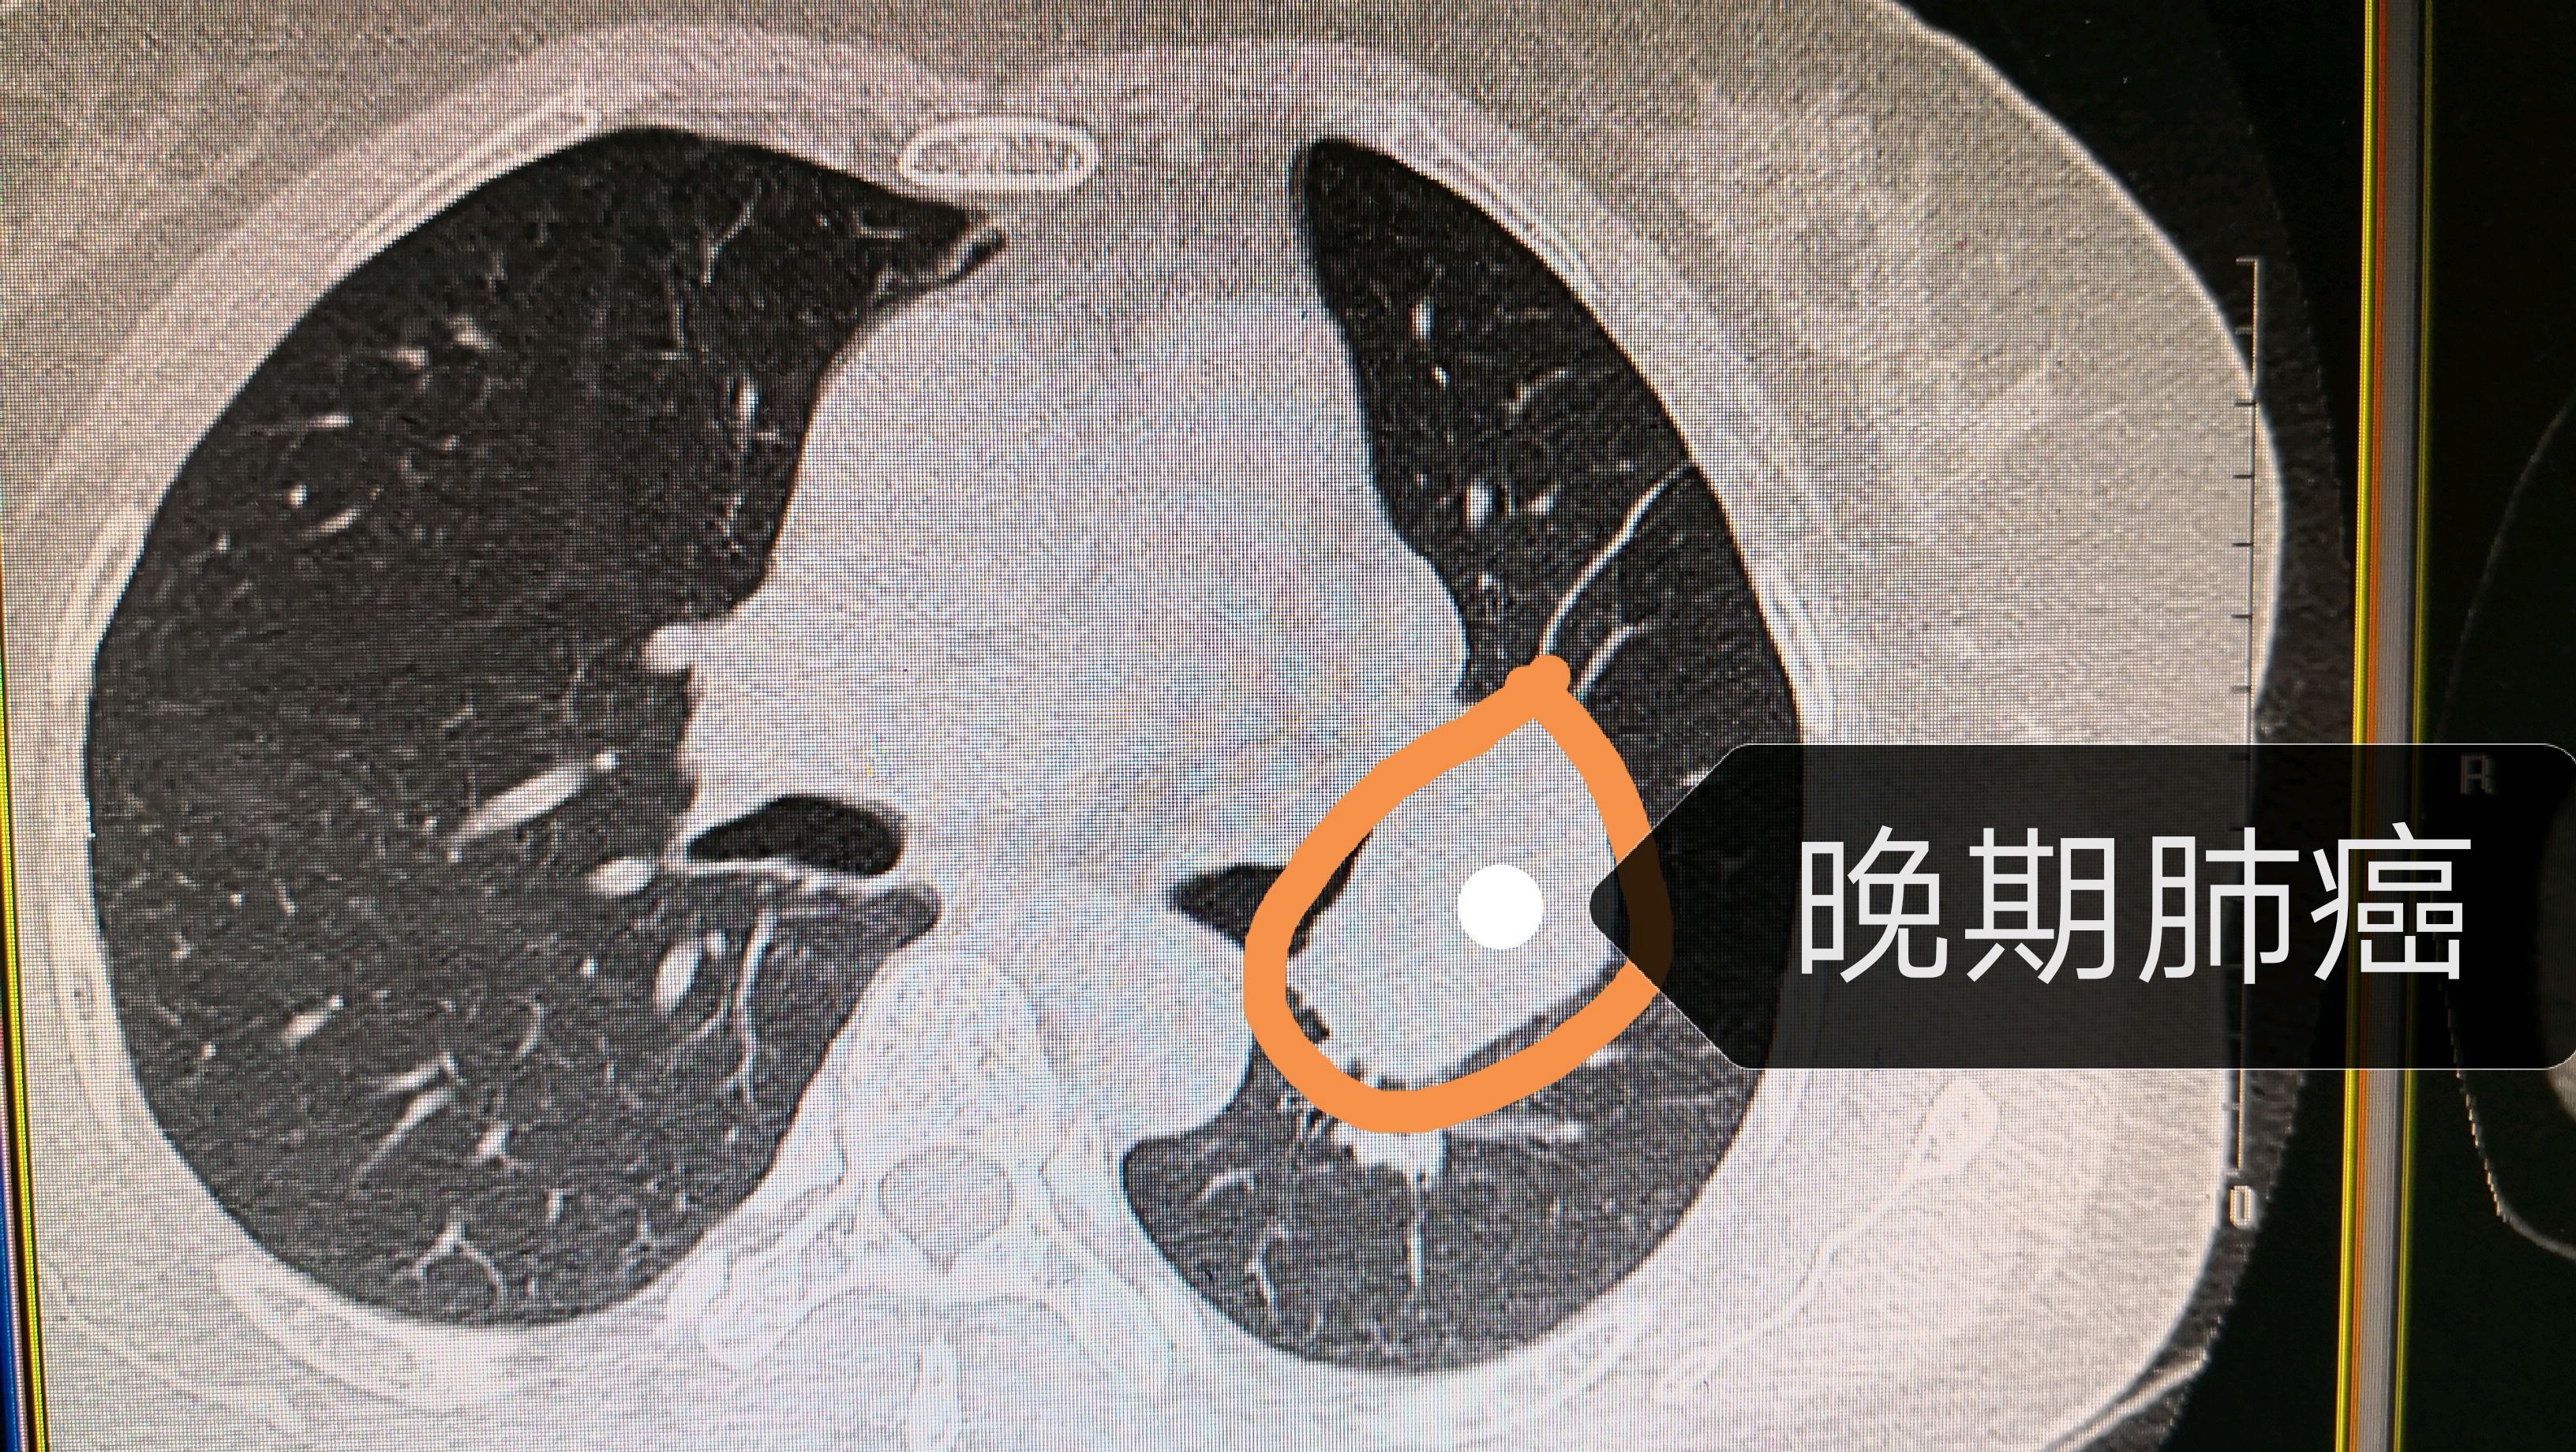

男性,吸烟多年,反复咳嗽,查胸部ct左肺占位,查气管镜确诊鳞癌